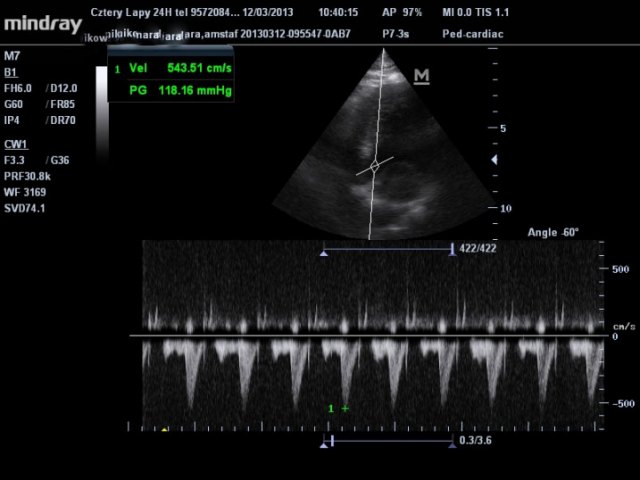

Zdecydowanie się badać! Każdy z nas może być na coś chory o czym nie ma zielonego pojęcia. Zaczynając przygodę ze sportem warto wykonać kilka badań, żeby przynajmniej wyeliminować podstawowe problemy, które później mogą prowadzić do nieszczęścia. Przede wszystkim należy zbadać swoje serce. To ona jest niesamowicie obciążone podczas wysiłku i odpowiada za niemal wszystkie tragiczne przypadki zgonów podczas biegania. Na początek musimy udać się na EKG. Koniecznie wynik musi analizować kardiolog, idealnie jak jest to kardiolog ze specjalizacją sportową. Ale takich ze świecą szukać. Jak już mamy EKG i wszystko jest w porządku to robimy sobie echo serca. Jest to niesamowicie ważne badanie i to na nim często wychodzą różne ukryte wady serca. Mając już taki zestaw z pozytywnymi wynikami możemy czuć się dużo bezpieczniej. Jednak nie zaszkodzi zrobić próby wysiłkowej z aparatem EKG. Tutaj również powinniśmy szukać lekarza, który zajmuje się badaniami sportowców. Ze swojego doświadczenia powiem, że robiłem coś takiego w Lux-Med i skończyło się na pulsie 135, szybciej bieżnia nie była w stanie pracować. Oczywiście takie badania to pieniądze wyrzucone w błoto… No i na koniec coś co powinniśmy badać regularnie, czyli morfologia. Naprawdę nie ma się czego bać, badanie nie jest specjalnie drogie a świetnie obrazuje większość problemów z naszym zdrowiem. Od tych najbardziej poważnych do zwykłego przeziębienia. Mamy już wszystkie badania, jesteśmy zdrowi i co teraz?